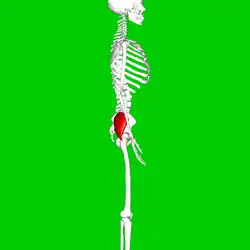

Hanche droite. Vue externe.

Hanche droite. Vue externe. Fémur droit. Vue postérieure.